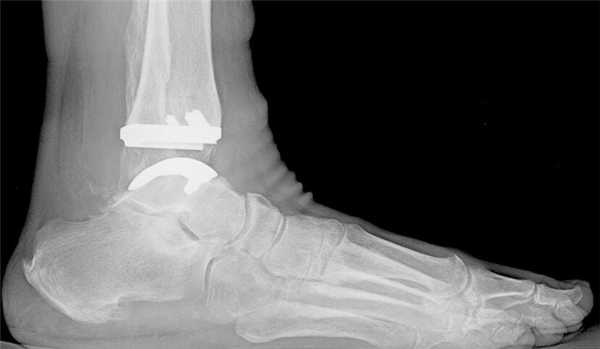

Рисунок 1 Рисунок 2 Рисунок 3

- При деформации голени или голеностопного сустава обязательна рентгенография с нагрузкой и с захватом голеностопного и коленного суставов (рис. 1)

- При наиболее сложных деформациях выполняется рентгенография в прямой проекции с захватом тазобедренного, коленного и голеностопного суставов (рис. 2)

- Магнитно-резонансная томография позволяет увидеть признаки артрита голеностопного и/или подтаранного суставов, которые не видны на рентгенограммах (рис. 3)